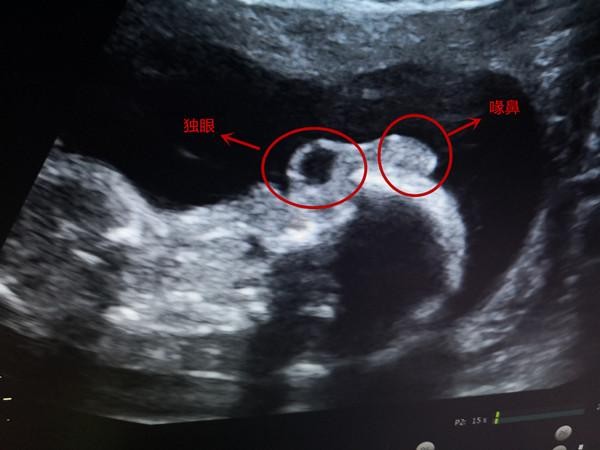

独眼喙鼻(产检发现畸形儿一只眼鹰钩鼻形似外星人)

扬子晚报网2月28日讯 (通讯员 刘威 记者朱鼎兆)整张脸上没有下颌,一只硕大的眼睛长在脸部中央,眼睛上方长出一个形似鹰嘴的鼻子,两个耳朵重合的出现在眼睛下面……..这样的描述很像是科幻电影中“外星人”的形象。近日,淮安市妇幼保健院超声科的医生在为一名孕妇做产检时,就发现了这样一个极其罕见的畸形胎儿。

33岁的唐女士(化名)是一名二胎孕妇,怀孕四个多月在当地医院产检时,医生发现胎儿长得有些“奇怪”,建议她去上级医院进一步诊断。超声发现孩子一个眼眶一只眼,没有正常的鼻子,而是一个喙鼻(鹰钩鼻),就是一个肉疙瘩没有鼻孔,长在眼睛的上方;没有下颌也看不到嘴,两个耳朵下移并且合并融合在颈前。据淮安市妇幼保健院产前超声诊断学组学术带头人孙宝娟介绍,是一个非常罕见的畸形,叫无下颌并耳畸形,这种畸形非常罕见,发生率约七万分之一,同时合并有颅内结构异常,是一个全前脑畸形,侧脑室是融合的,丘脑也是融合的,包括心脏的异常,有室间隔的缺损,此胎儿为严重致死性畸形,胎儿被查出后即被引产。

唐女士对于这个结果感到非常意外,因为第一个宝宝是正常的,她觉得二胎理论上也不会有问题。“现在的畸形多是多因素引起的,比如基因突变、病毒感染、环境的因素等,经常有第一胎正常的孕妇忽视二胎产检,定期产检非常重要。”孙宝娟告诉记者, 随着高龄产妇的增加,以及多种因素的印象,胎儿畸形率有所上升。据统计,2025年淮安市妇幼保健院共检出胎儿畸形400余例,为产科医生进行适当处理提供依据,降低了围产儿病死率及出生缺陷率,提高人口整体素质。她建议,每位孕妇妊娠期至少进行3次产科超声检查。